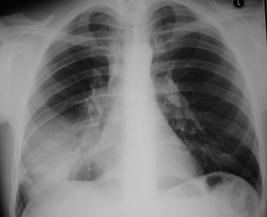

Рис.1. Очаговые тени